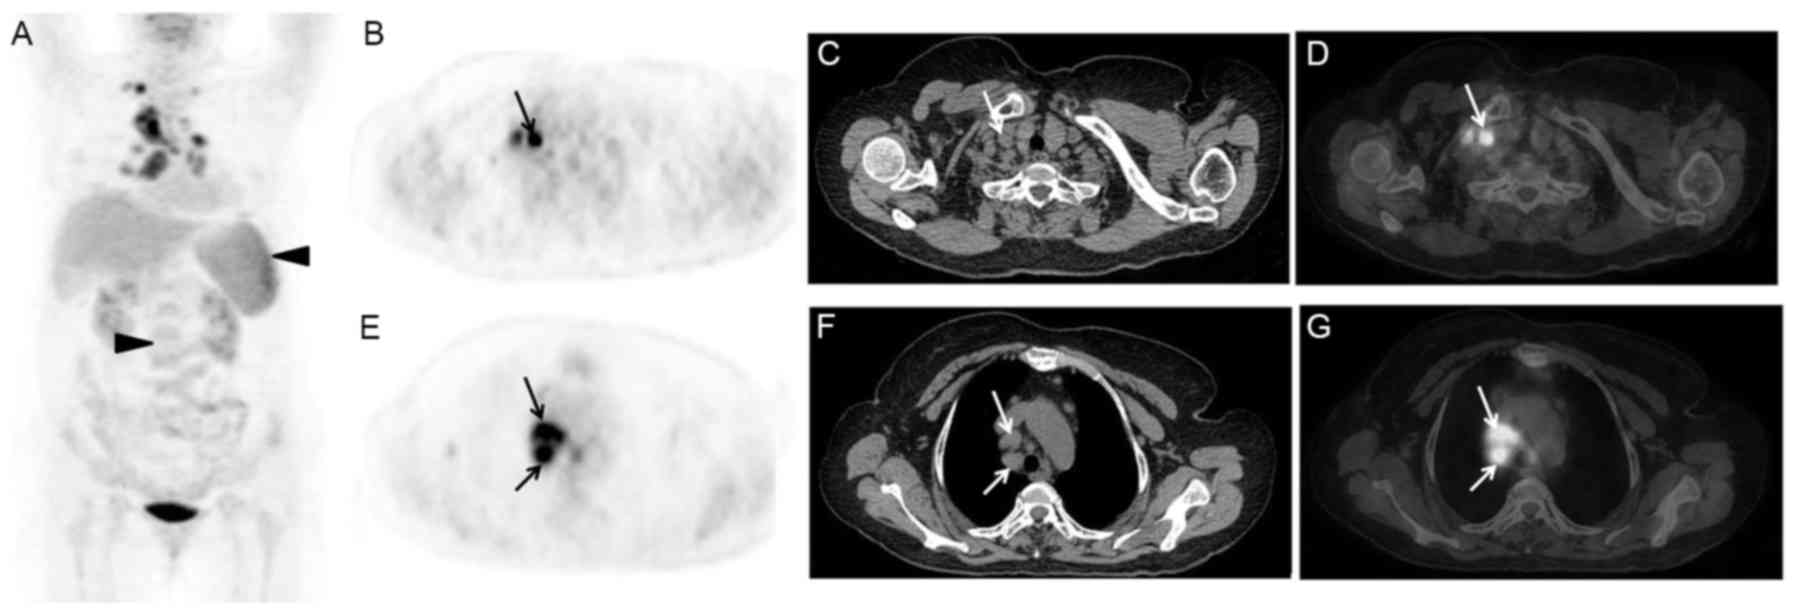

In addition, 1 case presented with marginally increased FDG uptake by the skin of the neck, shoulders and chest, which was caused by the skin rash of the corresponding part (Fig. 1). Another case displayed elevated FDG activity in the right shoulder joint, but the patient had no history of joint diseases. A total of 7 cases presented with effusion on the PET/CT images, including 4 cases with diffuse effusion (pleural, pericardial, abdominal and pelvic effusion; Fig. 2) and 3 cases with local effusion (2 patients with pericardial effusion and 1 patient with pelvic effusion). However, in the present study, no case of liver swelling and/or abnormal glucose metabolism was observed, and the mean SUVmax of the liver was 2.5±0.5 (range, 1.7–3.5).

Figure 1.

A 36-year-old female patient presented with intermittent fever (Tmax of 39.6°C) and rash for almost 1 year. AOSD was diagnosed 10 months ago, and the patient received the therapy of CSs. The rash was worsened after the reduction of CSs, and was widely located in the skin of trunk and limbs. 18F-FDG PET/CT images are presented: (A) MIP, (B) PET, (C) CT, (D) PET/CT, (E) PET, (F) CT, (G) PET/CT. These images indicated diffusely increased FDG uptake by the skin of the neck, shoulders and chest (arrows), with an SUVmax of 3.1. In addition, marginal swelling of the spleen was observed with diffuse FDG uptake. Lymph nodes of the left cervical, bilateral axillary (triangle arrows), lung hilar and abdominal regions were enlarged with mildly increased radioactivity, of which the SUVmax was 2.2. AOSD, adult onset Still's disease; CSs, corticosteroids; 18F-FDG, fluorodeoxyglucose; PET, positron emission tomography; CT, computerized tomography; MIP, maximum intensity projection; SUV, standardized uptake value.